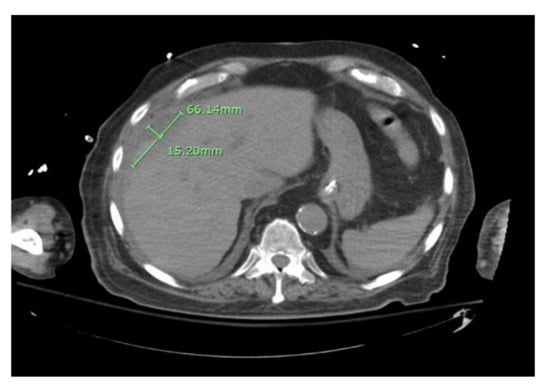

The patient underwent chest tube placement with the removal of 1600 cc of cloudy light-brown-colored fluid. Pleural fluid analysis was consistent with empyema, with WBC of 70,800 cells/mcL (61% neutrophils), glucose less than 10 mg/dL, LDH of 4821 IU/L, pH of 7.0, protein of 3.6 gm/dL, and Gram stain showing Gram-positive cocci in chains. Cytology was negative for malignant cells but showed severe acute inflammation and rare mesothelial cells. The blood culture on admission grew beta-hemolytic streptococci. The pleural fluid culture grew Streptococcus anginosus. On day two of hospitalization, the patient was scheduled for CT percutaneous drainage of liver abscess. However, the CT revealed a significant decrease in the size of the right subdiaphragmatic perihepatic collection to 1.5 cm in greatest thickness (Figure 4).

Figure 4. CT abdomen showing reduced size of the right sub-diaphragmatic perihepatic collection.